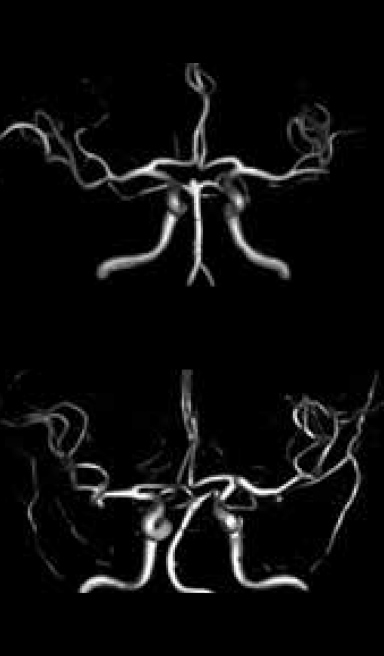

3D-TOF VR image

2D-TOF MIP image